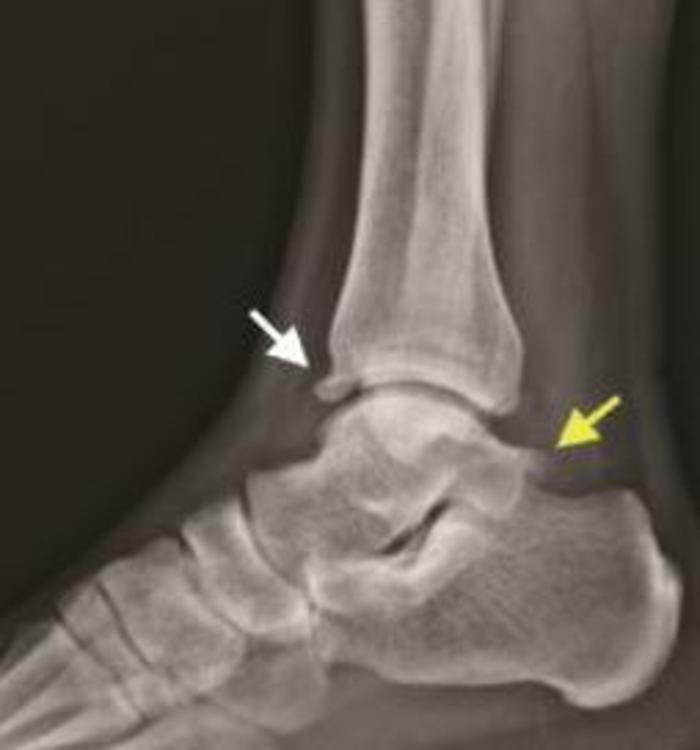

足球运动员和芭蕾舞演员中最常见,是运动员前踝疼痛的常见原因。踝关节前方有一个“凹槽样”结构,踝关节反复过度背屈时会在里面刺激生成骨赘,生成的骨赘会反过来限制踝关节的屈曲活动。X线侧位片可以观察到“鸟嘴样”骨赘形成,MRI是评估踝关节前方撞击综合征的主要方法,增生骨赘一般呈低信号。